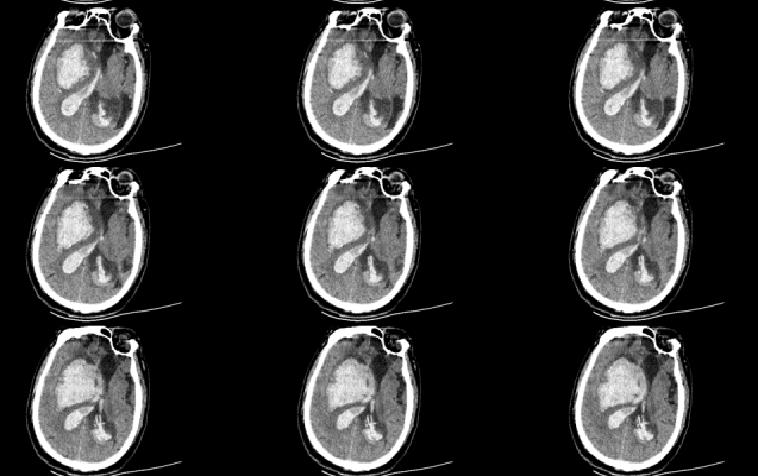

术后两周CT,未见脑积水,睁眼昏迷状态,转下级医院进一步康复治疗!